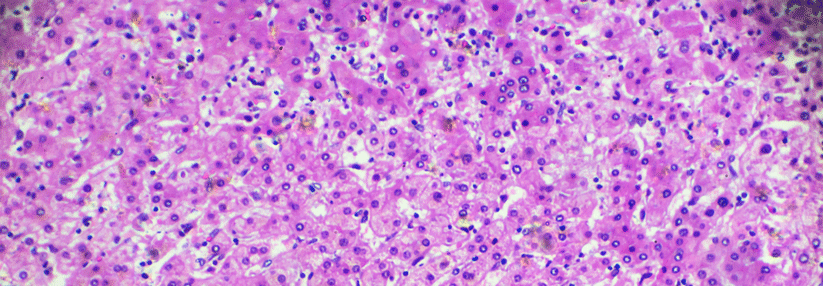

Mittlerweile gibt es auch beim Leberzellkarzinom einige gute Behandlungsmöglichkeiten. Mittlerweile gibt es auch beim Leberzellkarzinom einige gute Behandlungsmöglichkeiten. © wikimedia/Patho